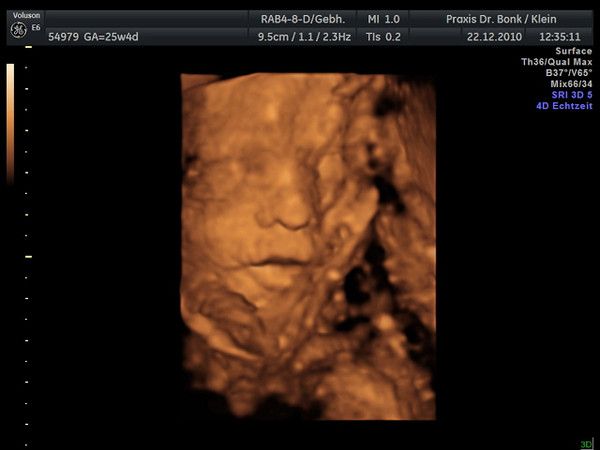

Krümmel bei der Nackenfaltenmessung, SSL 48,4 mm, man konnte schon richtig schön die Gesichtsform erkennen, vorallem die Stupsnase :-), Nackenfalte ist 1mm also unauffällig.